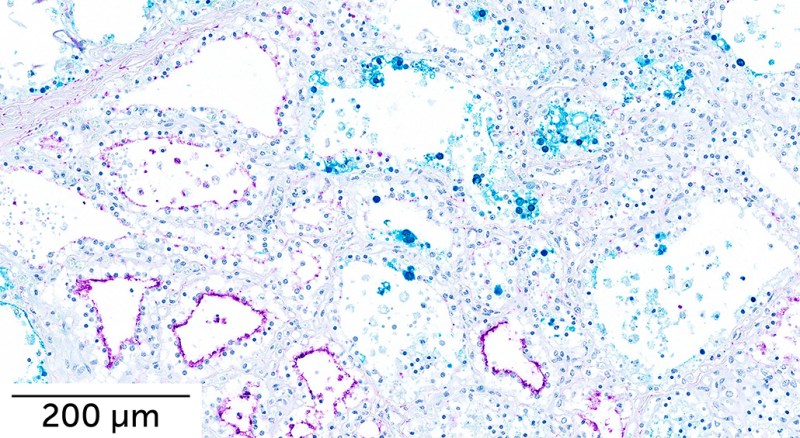

The virus has been detected in cow milk (SN: 4/25/24). The surface of cows’ mammary cells is covered in a ducklike protein that the bird flu virus can exploit to gain entry, researchers report in the July Emerging Infectious Diseases. Such infections might explain how the virus is spreading among cattle. It’s possible that contaminated milking equipment could carry virus from one cow’s udders to another, a separate group of researchers reported in the August Emerging Infectious Diseases.

In mice and ferrets, the virus spread to the lungs, as well as throughout the body to organs including the brain, intestines, kidney and heart. The virus also spread to the mammary glands of mice and some ferrets.